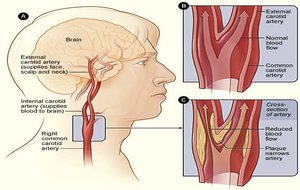

Ultrasonido Doppler

Carotideo Doppler